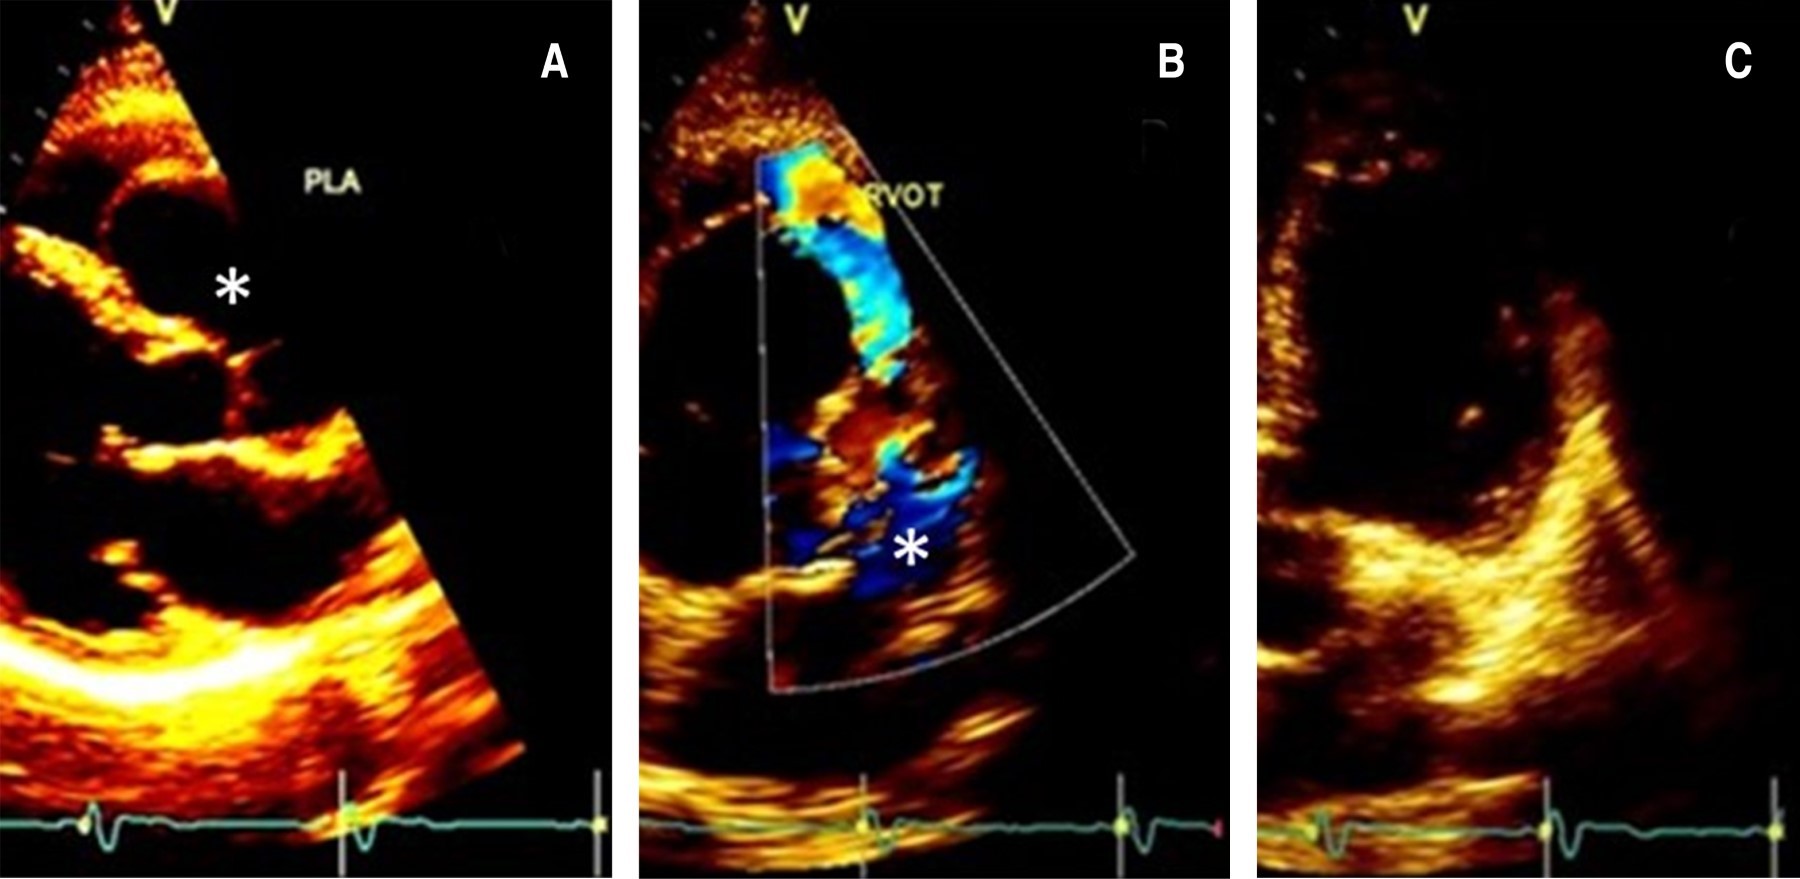

Los aneurismas del seno de Valsalva son dilataciones congénitas o adquiridas de la pared del seno aórtico a nivel justo por encima de las tres cúspides de la válvula aórtica, que pueden ser casos asintomáticos o fatales si se rompen, más frecuentemente hacia las cavidades cardiacas derechas. Estos casos son relativamente raros. Presentamos el caso de un varón de 72 años remitido por sospecha de soplo pulmonar. La evaluación reveló un aneurisma del seno de Valsalva derecho, que causaba compresión del tracto de salida del ventrículo derecho (TSVD). El ecocardiograma, la tomografía computarizada y el aortograma revelaron imágenes interesantes y evocadoras. El paciente recibió una reparación quirúrgica mid-cap. Este artículo revisa y discute la literatura actual y presenta el caso.

Figura 2